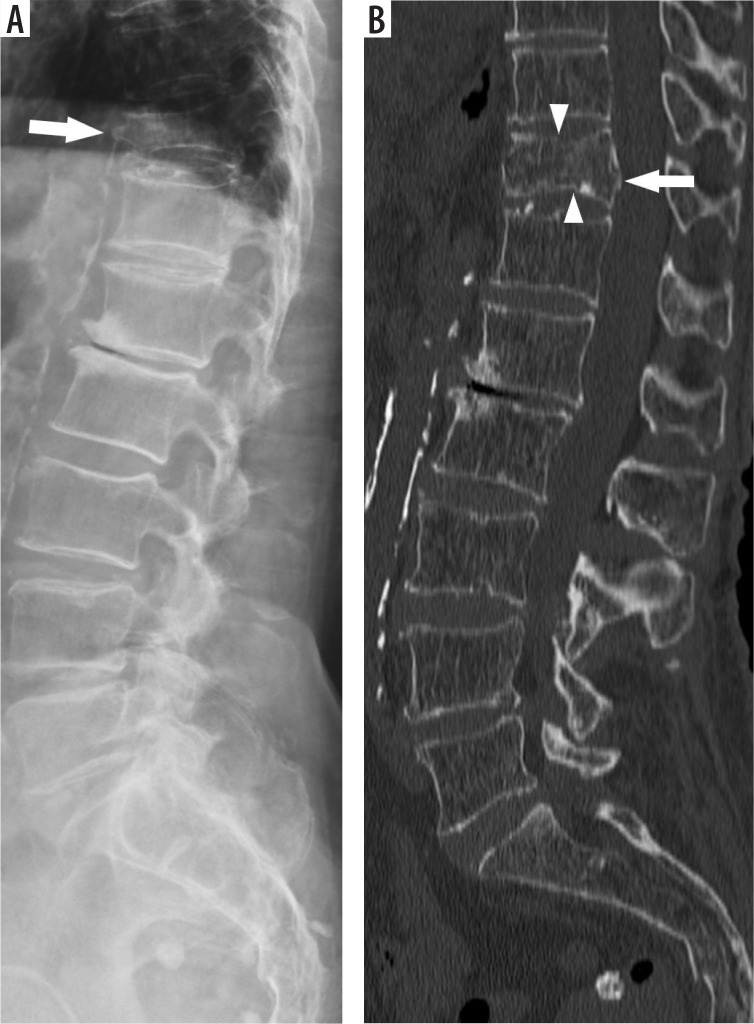

Purpose: To evaluate the diagnostic value of X-ray in detecting acute thoracolumbar (TL) fractures in minor trauma patients, using computed tomography (CT) as the reference standard, and to assess the impact of rigid spine conditions and reader experience on performance.

Material and methods: This retrospective single-centre study included patients with acute TL fractures from minor trauma between July 2014 and December 2020, who underwent both X-ray and CT. On CT, the presence or absence of rigid spine conditions, location, and fracture morphology were assessed. Two independent readers (a radiology resident and an attending radiologist) evaluated the radiographs, blinded to CTs. Sensitivity, specificity, and accuracy were calculated, and interobserver agreement was assessed using Cohen's κ coefficient.

Results: Sixty-three patients (32 with rigid spines, 31 without) with 84 fractures were included. The resident radiologist showed lower diagnostic accuracy than the attending radiologist, with more false positives in the rigid-spine group. In both groups, unrecognised fractures were more common for the resident radiologist (61.2% in rigid-spine patients and 48.6% in non-rigid-spine patients) compared to the attending radiologist (51.0% and 40.0%, respectively). Thoracic fractures were more frequently missed than lumbar fractures. Interobserver agreement was moderate (κ = 0.44) in the rigid-spine group and substantial (κ = 0.67) in the non-rigid-spine group.

Conclusions: Radiographs cannot reliably exclude unstable TL fractures in minor trauma patients. Attention should be paid to the lower thoracic region when evaluating lumbar radiographs.